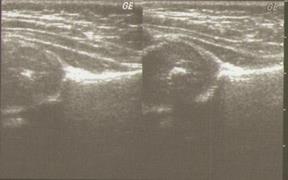

Рис. 6. Сонограмма тазобедренных суставов, вариант 2.